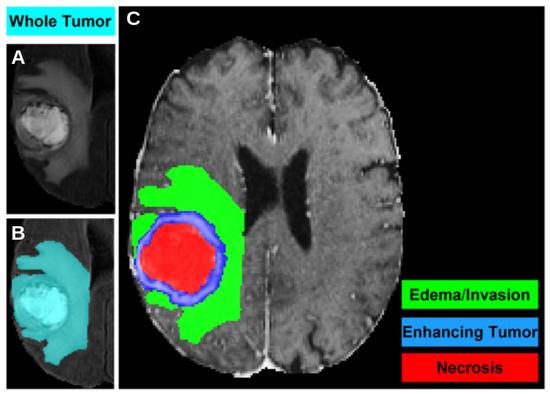

| Tumor Region | Dice Score |

|---|---|

| Whole Tumor | |

| Necrosis | |

| Edema | |

| Enhancing Tumor |